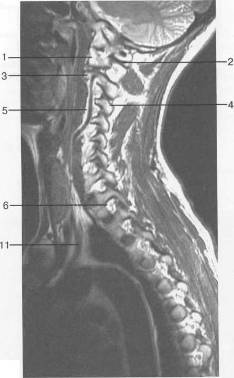

Рис. 13. МРТ. Парасагиттальное

изображение шейного отдела позвоночника. а-Т2-ВИ;б-Т1-ВИ.

- боковая масса С,; 2 - задняя

дуга С,; 3 - тело Сп; 4 - дуга Сш; 5 - позвоночная артерия на уровне сегмента V2;

6 - спинномозговой нерв; 7 - эпидуральная жировая клетчатка; 8 - тело Th,;

9 - ножка дуги Thn;

10 - аорта; 11 - подключичная артерия.